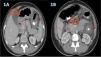

A 40-year-old woman, with a history of allergic rhinitis, was in the late puerperal period. She had not traveled recently or used herbal medicine or a new drug. She arrived at the emergency service because of abdominal pain and increasing abdominal distension, associated with diarrhea and vomiting. Hemogram identified marked eosinophilia (9.460x mm3) with no alteration in any other cell lines. Abdominal ultrasound revealed moderate ascites and fecal occult blood test was positive with no parasitosis. An abdominal tomography scan with contrast showed thickening of the gastric antrum, duodenum, and splenic flexure of the colon, with para-aortic and mesenteric adenomegaly and free intra-abdominal fluid (Fig. 1A and B). There were no thoracic alterations. Paracentesis was carried out, finding ascitic fluid with abundant inflammatory cellularity (Fig. 2A) (eosinophils 70%; neutrophils 10%; lymphocytes 3%; histiocytes 6%; plasmacytes 1%; and mesothelial cells 10%). There were no malignant cells, culture was negative, and the adenosine deaminase (ADA) level was 80 U/L. Esophagogastroduodenoscopy revealed very congestive gastroduodenal mucosa. Duodenal histopathology showed focal duodenal villous atrophy and countless eosinophils arranged in sheets, with glandular epithelium permeability (Fig. 2B). Colonoscopy was performed, taking random biopsies per segment, including the ileum. During the endoscopic study, no altered mucosa was identified, nor were there relevant findings in the reports. In other laboratory tests, IgE was found to be three-times above the upper limit of normal, accompanied by mild hypoalbuminemia. For the differential diagnosis, biochemical, hepatorenal, and electrolyte analyzes were carried out, along with tests for serum HIV, toxoplasma, vitamin B12, rheumatoid factor, antinuclear antibodies, antiDNA, ANCAs, serum tryptase, IgG, IgM, and IgA. All the results were within normal parameters. Flow cytometry in blood and immunohistochemistry of gastrointestinal tissues ruled out neoplastic involvement. The tuberculin skin test with PPD was nonreactive. The diagnostic conclusion was EGE and oral treatment with prednisone, 40 mg daily, was started. Symptoms resolved at 72 hours, abdominal distension decreased, and control for eosinophils in blood was normal at two weeks. The treatment was progressively suspended after eight weeks. The patient is currently asymptomatic with a normal eosinophil count and no abnormalities in the control contrast-enhanced magnetic resonance imaging of the abdomen and pelvis.